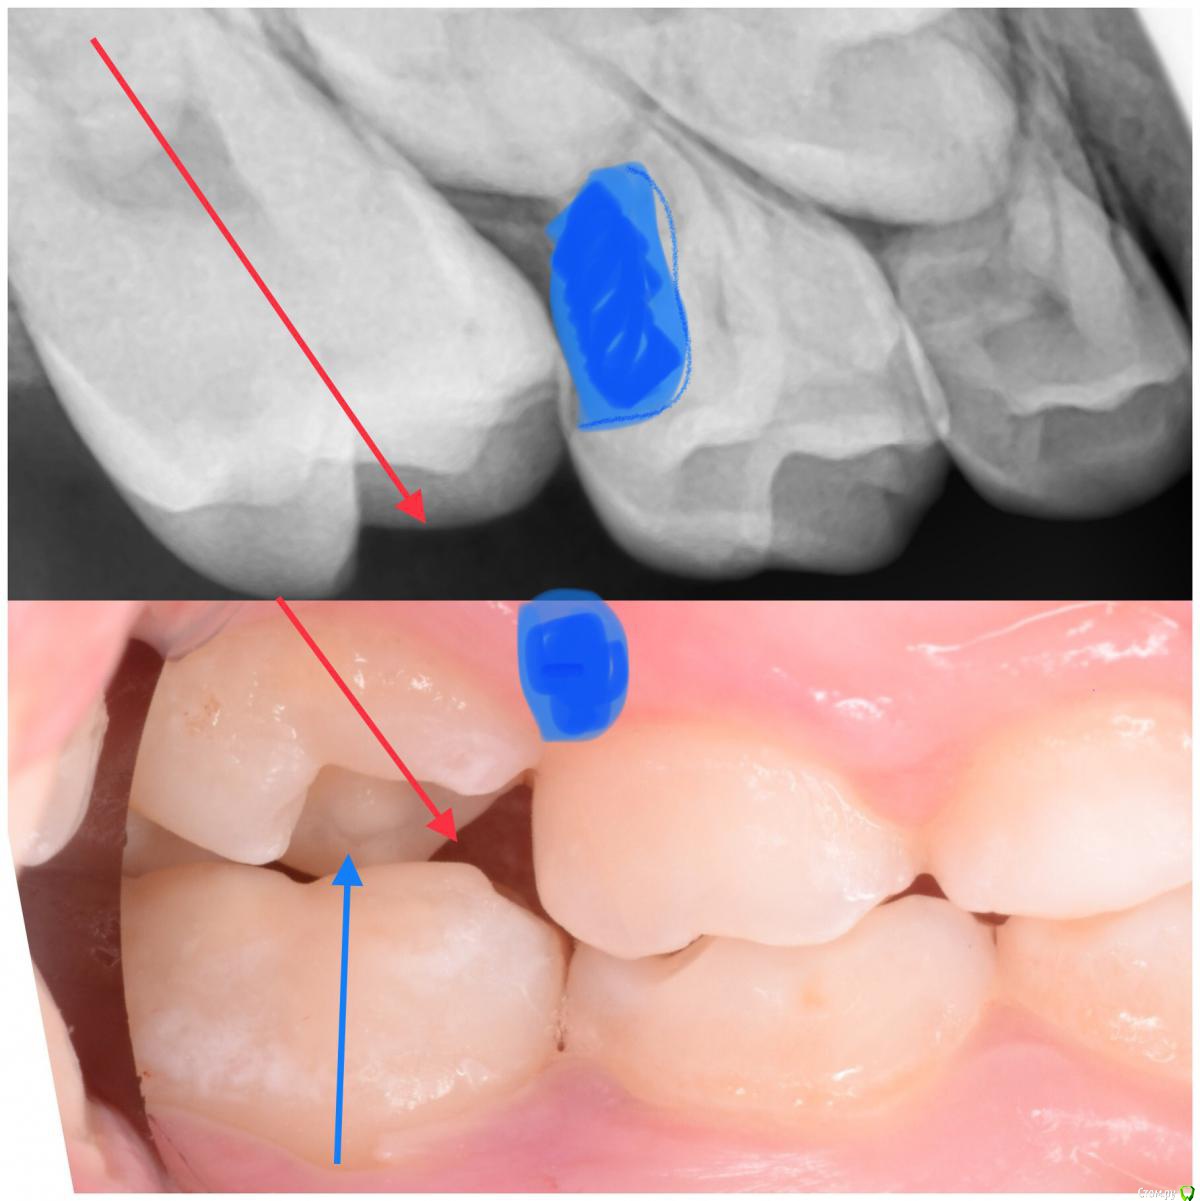

CRAZYDUCK Опубликовано 5 июня, 2018 Автор Поделиться Опубликовано 5 июня, 2018 Про эктопию верхних 6 зубов ( импактные шестые зубы). Встречается не так уж и редко . Для общего развития всем будет полезно . Эктопия ( импактные верхние 6 зубы).просто говоря - верхние 6 зубы из-за дефицита места на верхней челюсти или из-за оси прорезывания направленной медиально , способствуют резорбции корня 6.5 или 5.5. Эктопия может быть обратимой и необратимой . Но после 8 лет ( но возраст зубной может отличаться от антропометрического, поэтому смотрим на сроки прорезывания других постоянных зубов у конкретного ребёнка ) ортодонтическая коррекция нужна ( процесс необратимый). Методы устранения -Без удаления временного 5 возможно применение частичной брекет-системы , которая нормализует ось прорезывания 6 зуба ( в литературе можете найти всякие латунные сепараторы , но это история и мне кажется сложнее брекет-системы ). На первых двух фото показан случай эктопии 1.6 , который не требует удаления 5.5 . А вот дальше показан случай эктопии 2.6 , требующий удаления 6.5. Каждый случай индивидуален . ‼️коллеги , важно помнить , что 2.6 в случае удаления 6.5 полностью заблокирует зачаток 2.5 ‼️здесь обязательно нужна будет помощь ортодонта ( немедленная или отсроченная ортодонт с родителями решат ). Ну а 5 временные зубы после такой подлости со стороны шестёрок могут быть причиной воспаления ( хотя сами пятые могут быть инактными ). 2 Ссылка на комментарий

CRAZYDUCK Опубликовано 5 июня, 2018 Автор Поделиться Опубликовано 5 июня, 2018 (изменено) Про эктопию верхних 6 зубов . Изменено 5 июня, 2018 пользователем CRAZYDUCK Ссылка на комментарий